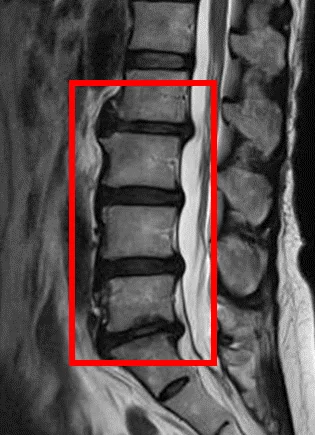

По данным МРТ и результатам осмотра пациента выявлена дегенерация межпозвоночных дисков L2/L3, L3/L4, L4/L5 и L5/S1, а также стеноз межпозвонковых отверстий.

В клинике проведена селлгель-терапия на четырех межпозвоночных дисках (L2/L3, L3/L4, L4/L5, L5/S1).